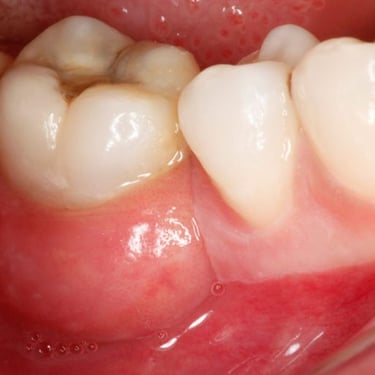

Pulpitis Crónica Hiperplásica

La pulpitis crónica hiperplásica es una inflamación de la pulpa con crecimiento excesivo de tejido pulpar a través de una caries abierta.

Los pacientes notan un tejido rojo que sobresale de la cavidad dental.

El tratamiento incluye la eliminación del tejido afectado y un tratamiento de conducto. Es crucial tratar la caries para evitar infecciones adicionales.